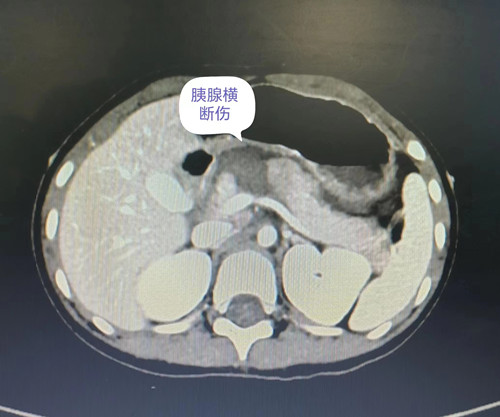

小洁入院后,儿童重症医学科立即开展诊疗工作。禁食、补液,急诊完善检查,请会诊等。孩子腹部CT提示胰腺横断伤、主胰管断裂,胰液渗入了腹腔,持续进展随时可危及生命。更为关键的是,胰腺损伤可导致组织坏死,手术难度大,更难的是如何保护孩子的胰腺功能,以防在其成长过程中出现代谢问题。